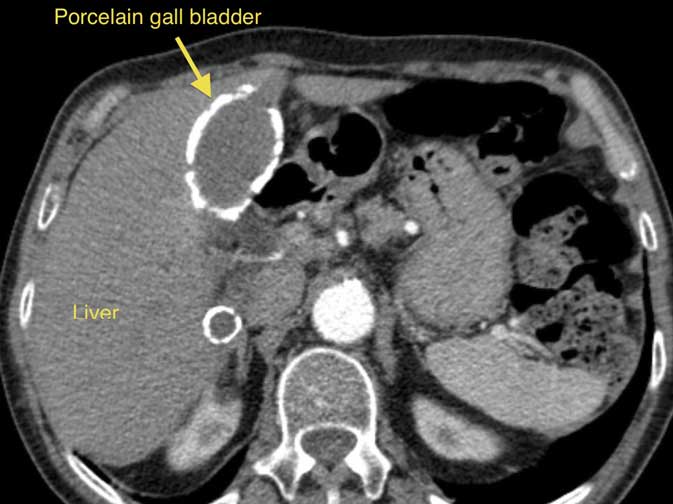

Calcium deposits in the wall of the gall bladder (a consequence of chronic inflammation), described as Porcelain gall bladder, increase the risk of gall bladder cancer. The picture on this page shows a CT scan, with a porcelain gall bladder clearly visible (you can click on the picture to enlarge it).